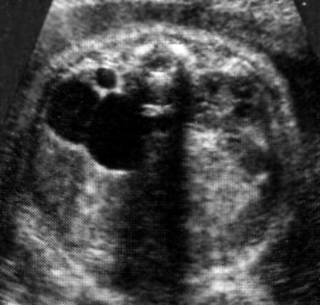

Εντερική απόφραξη

Υπερηχογραφικά, φυσιολογικά ο αυλός του λεπτού και του παχέος εντέρου δεν ξεπερνούν

τα 7mm και 20mm αντίστοιχα.

Η απόφραξη μπορεί να είναι ενδογενής (ατρησία ή στένωση εντερικού αυλού), ή

εξωγενής (εγκολεασμός, ειλεός, απουσία γαγγλίων).

Παρατηρείται σε 1 κάθε 2.000 γεννήσεις. Στις μισές περιπτώσεις πρόκειται για

απόφραξη λεπτού εντέρου και στις άλλες μισές για ατρησία ορθού - πρωκτού. Η

πιο συχνή θέση απόφραξης είναι ο τελικός ειλεός (35%). Στο 5% των περιπτώσεων

υπάρχει απόφραξη σε πολλαπλά σημεία.

Η απόφραξη του λεπτού εντέρου είναι συνήθως σποραδική και χρωμοσωμικές ανωμαλίες

είναι σπάνιες. Η διάγνωση της απόφραξης λεπτού εντέρου γίνεται συνήθως μετά

τις 25 εβδομάδες, καθώς η διάταση του εντερικού αυλού είναι προοδευτική. Η κοιλία

είναι διατεταμένη, με πολλαπλές εντερικές έλικες γεμάτες υγρό (εικόνα 21). Υδράμνιο

συνοδεύει συνήθως τις υψηλές αποφράξεις. Εάν συμβεί διάτρηση του εντέρου, μπορεί

να παρατηρηθεί παροδικά ασκίτης, περιτονίτιδα από μηκώνιο, ή σχηματισμός κύστης

από μηκώνιο. Η διαφορική διάγνωση περιλαμβάνει ανωμαλίες ουροποιητικού συστήματος,

μεσεντερικές, ωοθηκικές και εντερικές κύστεις.

| Εικόνα 20. Ατρησία 12δακτύλου. | Εικόνα 21. Ατρησία ειλεού. |